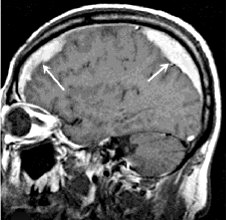

МРТ головного мозга. Массивная двухсторонняя хроническая субдуральная гематома.

Ключевыми методами диагностики субдуральной гематомы являются КТ и МРТ головного мозга. Для острых гематом предпочтительнее КТ, которая показывает однородную зону повышенной плотности серповидной формы. Со временем гематома разуплотняется, и через 1-6 недель она перестает отличаться по плотности от окружающих тканей. В таких случаях диагноз основывается на смещении латеральных отделов мозга в медиальном направлении и признаках сдавления бокового желудочка.

При МРТ может наблюдаться пониженная контрастность зоны острой гематомы, тогда как хронические субдуральные гематомы обычно имеют гиперинтенсивность в Т2 режиме. В сложных случаях помогает МРТ с контрастированием: интенсивное накопление контраста капсулой гематомы позволяет дифференцировать ее от арахноидальной кисты или субдуральной гигромы.